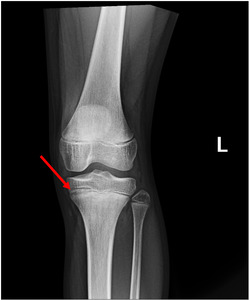

Osgood Schlatter disease (OSD) is characterized by pain at the tibia. Clinical symptoms include pain in the knee and trouble with mobility. Since OSD is often seen in growing kids who practice repetitive physical activities, it is commonly treated by applying ice on the knee, regularly stretching the knee, and limiting physical activity (Figure 3).